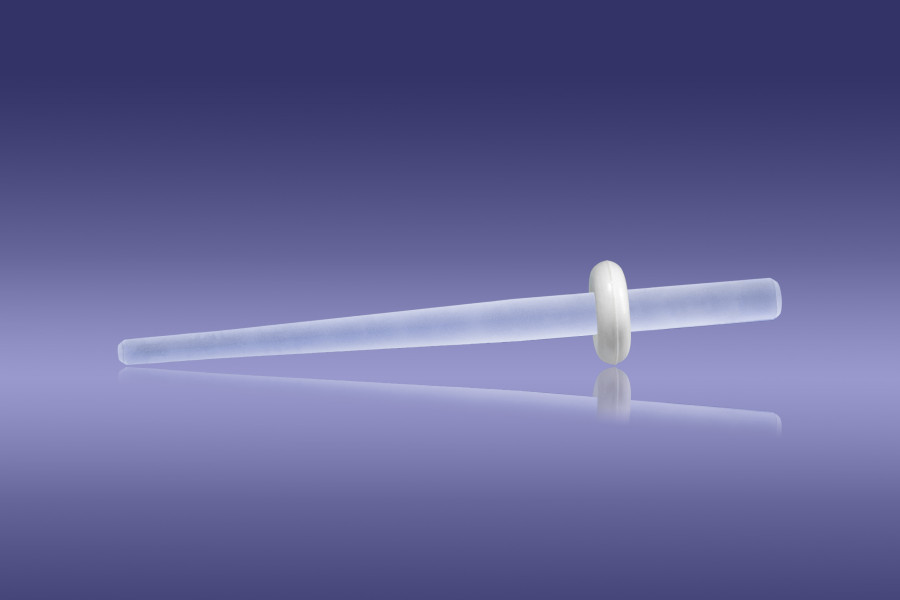

Posts

3 posts from red

5 posts from yellow

5 posts from white

5 posts from blue

3 posts from black